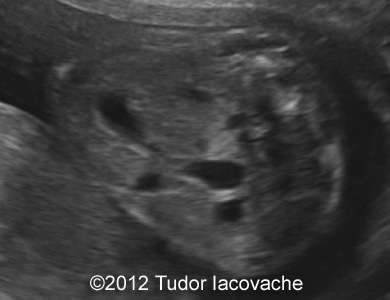

At 22 weeks the scan was suggestive of duodenal stenosis, with "double bubble" sign , no other anomalies, normal amniotic fluid. Karyotype was performed and was normal 46XX. The pregnancy continued with no problems and normal amniotic fluid.

The images and video clip are of the 22-week scan and shows the typical double bubble with dilation of the proximal duodenum and communication with the stomach.

Image 1-4: